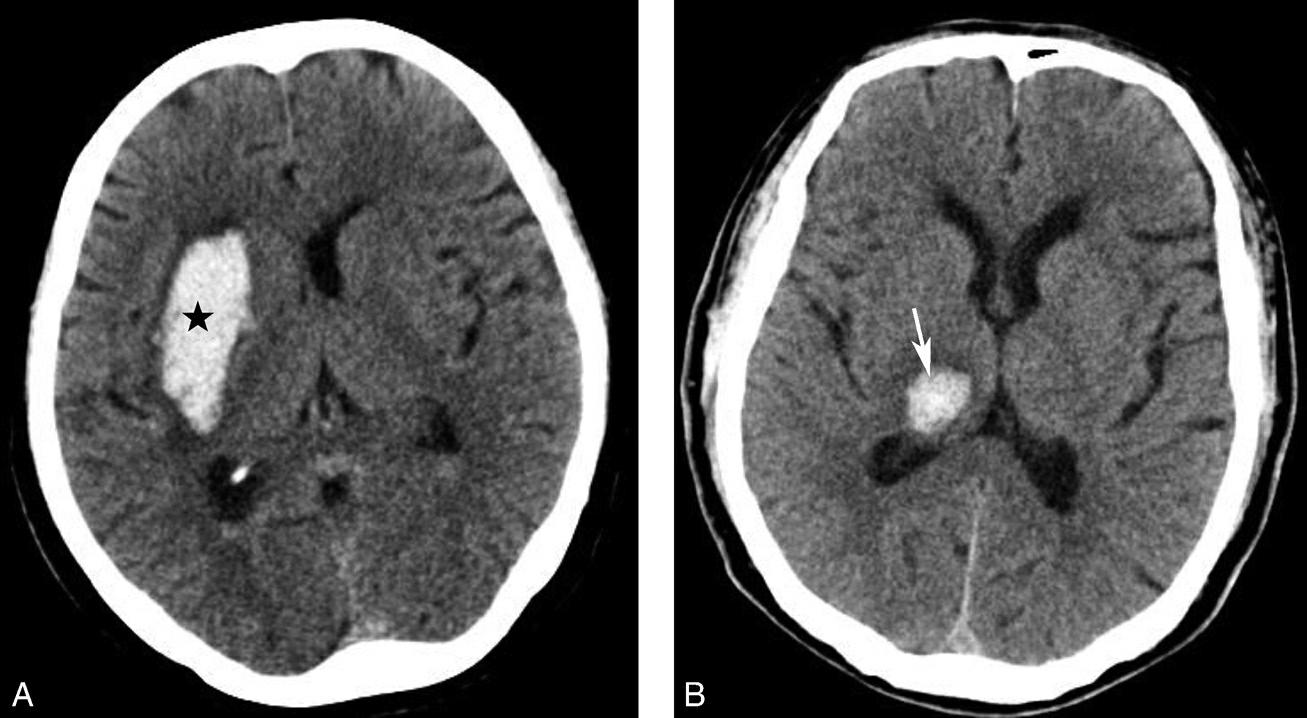

图1-2-20 环池闭塞

右侧颞叶脑内大血肿(★),产生严重的占位效应,环池受压闭塞(箭),脑疝形成

基底节为脑卒中的好发部位,与纹状动脉的解剖特点有关,深穿支动脉的破裂和栓塞可分别引起基底节区的出血和梗死(图1-2-32、图1-2-33)。

图1-2-32 脑出血

A.右侧壳核脑出血,形成高密度血肿(★);B.右侧丘脑出血,呈球形高密度影(箭)